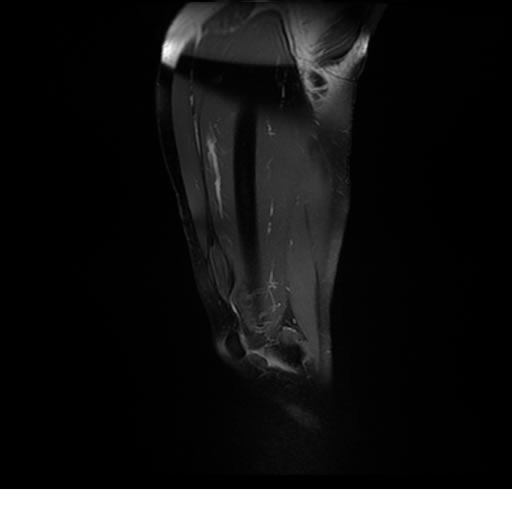

Se realiza estudio de MRI de pierna izquierda, utilizando secuencias Spin Echo y GRE en diferentes planos, se realiza angio MRI en fase arterial y venosa de pierna izquierda

El estudio demuestra masa a nivel de los músculos gemelos, más evidente en secuencia con pulso de saturación de grasa, en el estudio de angio resonancia de pierna la fase arterial no muestra ninguna anormalidad, en la fase venosa se observa acumulo del medio de contraste a este nivel.

Se concluye que se observa una masa de tejido muscular sumamente vascularizada compatible con un hemangioarcoma.